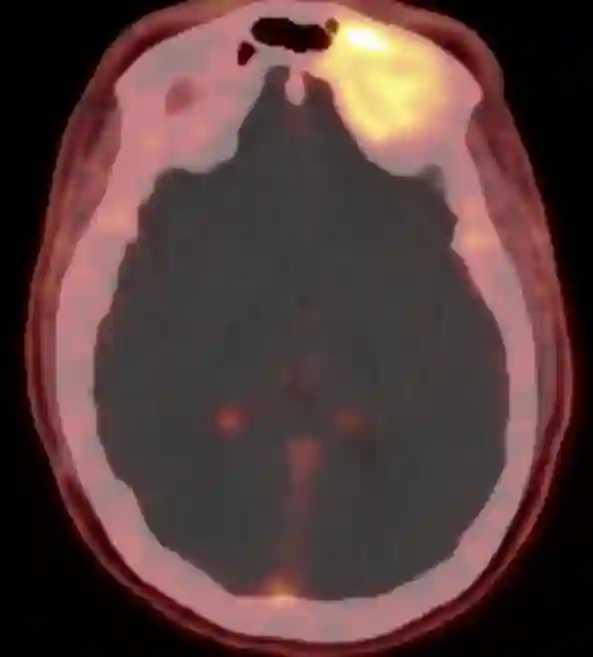

68Ga-DOTATOC PET CT bei einem Patienten mit einem histopathologisch verifizierten Meningeom.